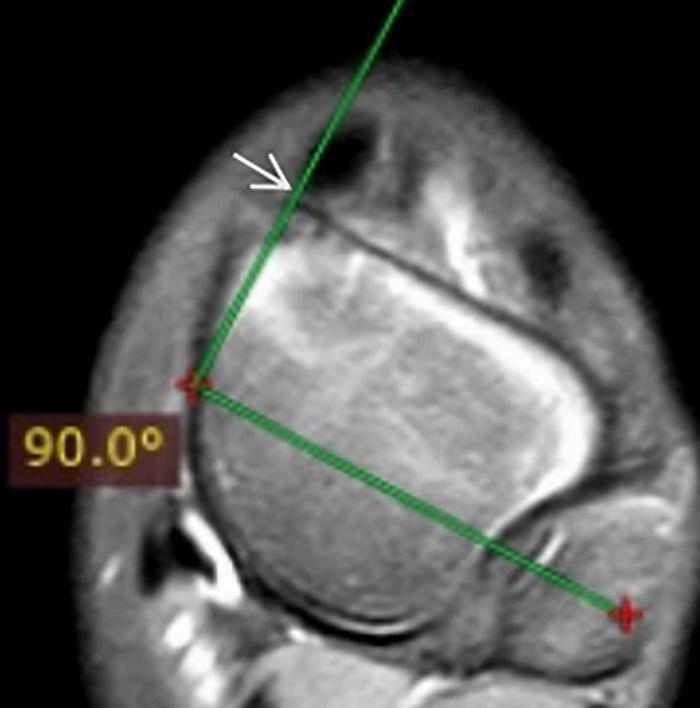

This is a retrospective study of fifteen children with clubfeet who were treated with the Ponseti method. MRI studies were obtained using a 3.0T Machine (GE Healthcare, United States). T1-weighted and T2-weighted images were acquired in the standard anatomic sagittal, transverse, and coronal planes. For the measurement, the best slice that clearly demonstrated the anatomy was chosen. Sagittal talocalcaneal angle, sagittal tibiocalcaneal angle, coronal tibiocalcaneal angle, transverse talar neck angle, transverse talonavicular angle, and transverse talocalcaneal angle were measured. The eighteen corrected clubfeet were compared with the twelve unilateral normal feet at clinical and radiological levels using a Pirani scoring system and MRI, respectively.

In total, 15 cases (twelve boys and three girls) with clubfeet were examined by using MRI. Twelve cases had unilateral and three had bilateral involvement (eleven left clubfeet and seven right clubfeet), giving a total of eighteen clubfeet when compared with twelve normal feet. The mean age of patients at examination was 47.7 months (8-96 months). The recovery of the corrected clubfoot in these patients met the goals of Ponseti treatment (functional, normal looking, pain-free, and plantigrade foot). Before Ponseti treatment, the mean Pirani score of clubfoot was 5.5 (5-6). During this follow-up, the Pirani score was 0.07 (0-0.05). The results of the MRI indicated that only the transverse talonavicular angle showed a significant difference between the treated clubfeet and the normal feet ( < 0.001). One case had dorsal talonavicular subluxation in the sagittal plane and had the lateral subluxation of the navicular in the transverse plane, which has never been reported in previous studies.

Although the appearance and function of clubfoot were recovered well after the Ponseti method, the results of MRI indicated that the Ponseti method successfully corrected the varus, cavus, and equinus deformities and incompletely corrected the adduction deformity regarding transverse talonavicular angle. At the same time, the Ponseti method may cause dorsal talonavicular subluxation in the sagittal plane and lateral subluxation of the navicular in the transverse plane on MRI.

这是一项对15例接受庞塞蒂方法治疗的马蹄内翻足患儿的回顾性研究。使用3.0T机器(美国通用电气医疗集团)进行MRI检查。在标准解剖矢状面、横断面和冠状面获取T1加权和T2加权图像。为进行测量,选择能清晰显示解剖结构的最佳层面。测量矢状面距跟角、矢状面胫跟角、冠状面胫跟角、横断面距骨颈角、横断面距舟角和横断面距跟角。分别使用皮拉尼评分系统和MRI在临床和影像学层面将18例矫正后的马蹄内翻足与12例单侧正常足进行比较。

总共对15例(12例男孩和3例女孩)马蹄内翻足患儿进行了MRI检查。12例为单侧受累,3例为双侧受累(11例左侧马蹄内翻足和7例右侧马蹄内翻足),与12例正常足相比,共有18例马蹄内翻足。检查时患者的平均年龄为47.7个月(8 - 96个月)。这些患者矫正后的马蹄内翻足恢复情况达到了庞塞蒂治疗的目标(功能正常、外观正常、无痛且足能放平)。在庞塞蒂治疗前,马蹄内翻足的平均皮拉尼评分为5.5(5 - 6)。在此次随访期间,皮拉尼评分为0.07(0 - 0.05)。MRI结果表明,仅横断面距舟角在治疗后的马蹄内翻足与正常足之间存在显著差异(<0.001)。1例在矢状面有距舟背侧半脱位,在横断面有舟骨外侧半脱位,这在以往研究中从未有过报道。

尽管采用庞塞蒂方法后马蹄内翻足的外观和功能恢复良好,但MRI结果表明,庞塞蒂方法成功矫正了内翻、高弓和马蹄畸形,但在横断面距舟角方面内收畸形未完全矫正。同时,庞塞蒂方法在MRI上可能导致矢状面距舟背侧半脱位和横断面舟骨外侧半脱位。